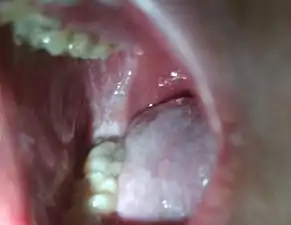

Koplik's spots seen inside the mouth are diagnostic for measles, but are temporary and therefore rarely seen.[28] Koplik spots are small white spots that are commonly seen on the inside of the cheeks opposite the molars.[27] They appear as "grains of salt on a reddish background."[30] Recognizing these spots before a person reaches their maximum infectiousness can help reduce the spread of the disease.[31]

Koplik's spots on the third pre-eruptive day

Koplik's spots on the day of measles rash.